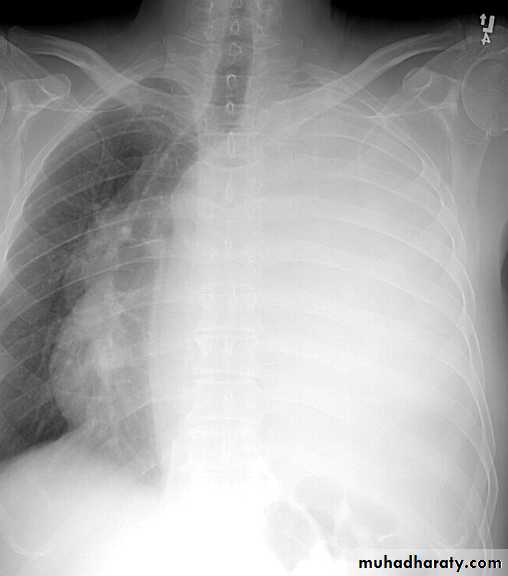

CXR:

closed Pneumothorax

Tension Pnenmothorax

What is the difference??

Massive effusion

Whole lung atelectasisEmpyema